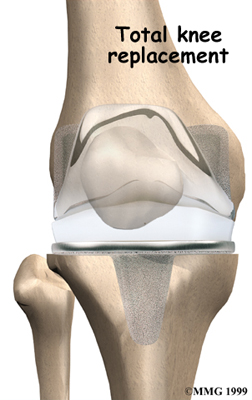

Artificial Knee Replacement

An artificial knee replacement is the ultimate solution for advanced knee OA.

Surgeons prefer not to put a new knee joint in patients younger than 60. This is because younger patients are generally more active and might put too much stress on the joint, causing it to loosen or even crack. A revision surgery to replace a damaged prosthesis is harder to do, has more possible complications, and is usually less successful than a first-time joint replacement surgery.

Related Document: FYZICAL West Fort Myers Guide to Artificial Joint Replacement of the Knee